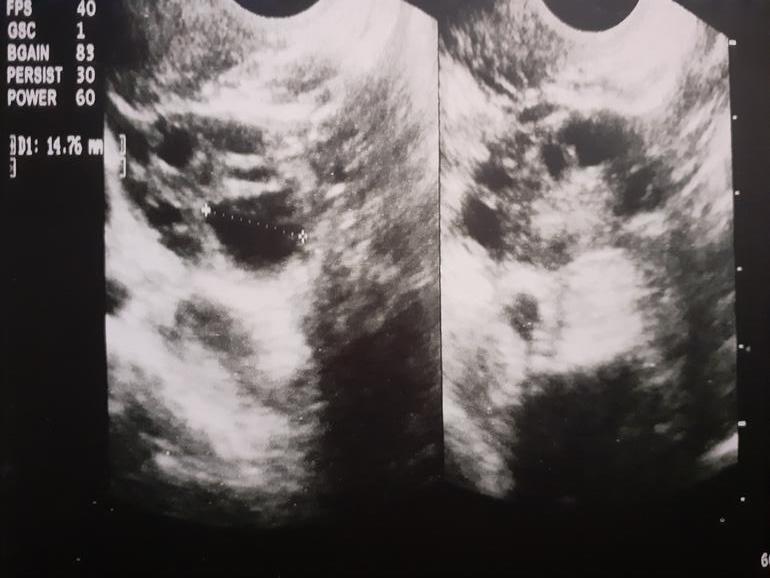

Во вторник 2.07 сделали операцию на яичниках, делали насечки. Врач сказал классический СПКЯ, оболочка твердая (надо было давно сделать операцию и бедные были мои яичники- это его слова) 👀 Врач сам не ожидал, что все будет так запущено, ведь УЗИ не увидело и половины картины. Восстановление быстрое, дома со вчерашнего дня..17 числа едим на море, врач убедил, что 15 ого уже смогу, хоть нырять в горную реку и забыть про операцию, но я конечно переживаю. Пью антибиотик, Серрату,Циклоденон и свечи биострепта. Сказал, что после моря нужен клостилбегит на 5 дней. Но половой покой только до 15.07... Сказал, что предохраняться не нужно, если планируем б. Вот теперь голову ломаю. А если я приеду с моря уже беременна? Клостилбегит же может навредить? Ясное дело будет, если начнутся месячные, тогда я на пятый ДЦ просто начну его пить...а если нет?! Что тогда? Подскажите девочки, кто-то сталкивался? Получилось ли?🙏